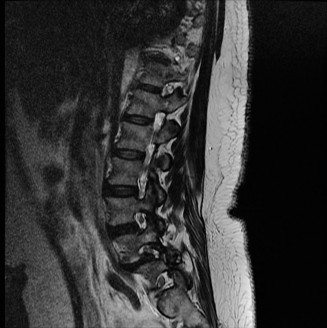

Prognosis of central cord syndrome? Indications for surgery for this disorder? CASE 2 A 56-year-old man presents to you with a chief complaint of severe right buttock, posterior thigh, and lower leg pain for 12 weeks. It radiates to the lateral aspect of his foot, and it is worse with sitting or standing for prolonged periods and with walking. Now over the past 2 weeks, he reports difficulty with toe push-off on the right side. Treatment so far has been nonsteroidal anti-inflammatory drugs (NSAID), physical therapy, and an epidural injection without significant relief. Physical examination findings include 4/5 right ankle plantar flexion, a positive straight leg raise on the right, and an absent right Achilles tendon reflex. Images of his lumbar spine are shown in Figures 1–4 and 1–5.

Figure 1–5

The correct answer is (C). The patient presents with classic right S1 radiculopathy and new onset plantar flexion weakness. The images demonstrate a right-sided paracentral disc herniation at L5/S1 compressing the traversing S1 nerve root. Despite nonoperative management, he continues to have severe pain and new weakness. Continued physical therapy or an epidural injection is unlikely to improve the patient’s pain at this time. In the setting of neurological decline, surgery is more strongly indicated. Lumbar discectomy is the most appropriate procedure for this patient. Fusion would only be indicated if there were radiographic signs of instability, which are not present.